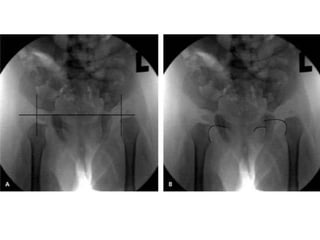

Von-Rosen II Belirtisi

• Kalçalar ekstansiyonda, 45-50° abduksiyon ve

25° iç rotasyonda iken ön-arka grafi çekilirse

normalde femur cismi uzun aksı asetabulumun

üst dış kenarından geçer. GKD’de bu hat

asetabulumun üst dış kenarının üzerine çıkar,

spina iliaka anterior süperiordan geçer.

Von-Rosen II Belirtisi •Kalçalar ekstansiyonda, 45-50° abduksiyon ve 25° iç rotasyonda iken ön-arka grafi çekilirse normalde femur cismi uzun aksı asetabulumun üst dış kenarından geçer. GKD’de bu hat asetabulumun üst dış kenarının üzerine çıkar, spina iliaka anterior süperiordan geçer.